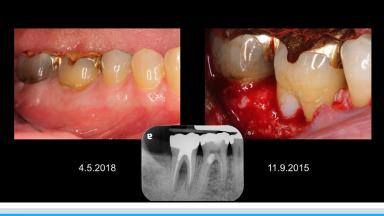

歯根の外部吸収は外傷、過剰なルートプレーニング、ウォーキングブリーチなどによって引き起こされる。外部歯根吸収は外部表面吸収、外部炎症性吸収、外部置換吸収、外部歯頚部吸収に分類することができる。演者は自身の症例を通して、それぞれのタイプにおける歯根外部吸収への対応法について紹介している。